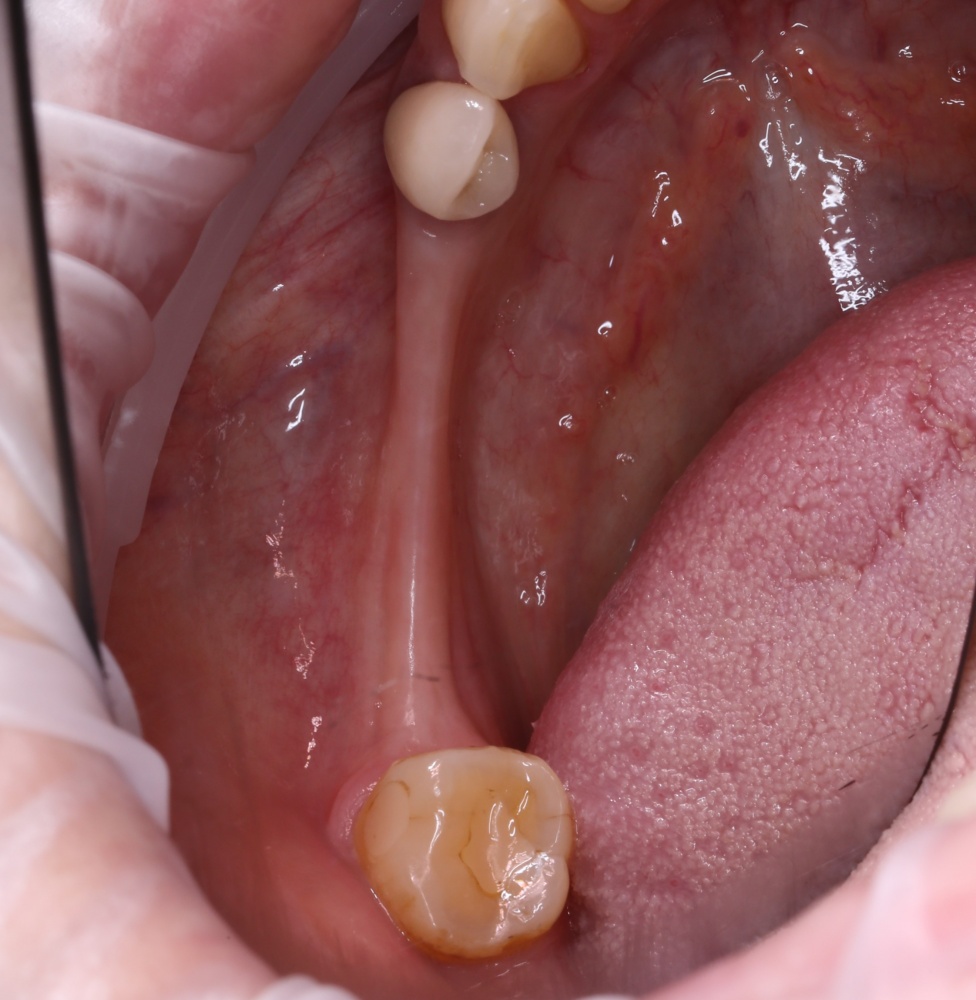

Обычно, через день после операции рана выглядит вот таким образом:

А сам пациент — как-то так:

Отёк, болезненные ощущения, затрудненное открывание рта — вполне себе обычная симптоматика после подобных операций. Впрочем, как и после остеопластик другими методами.